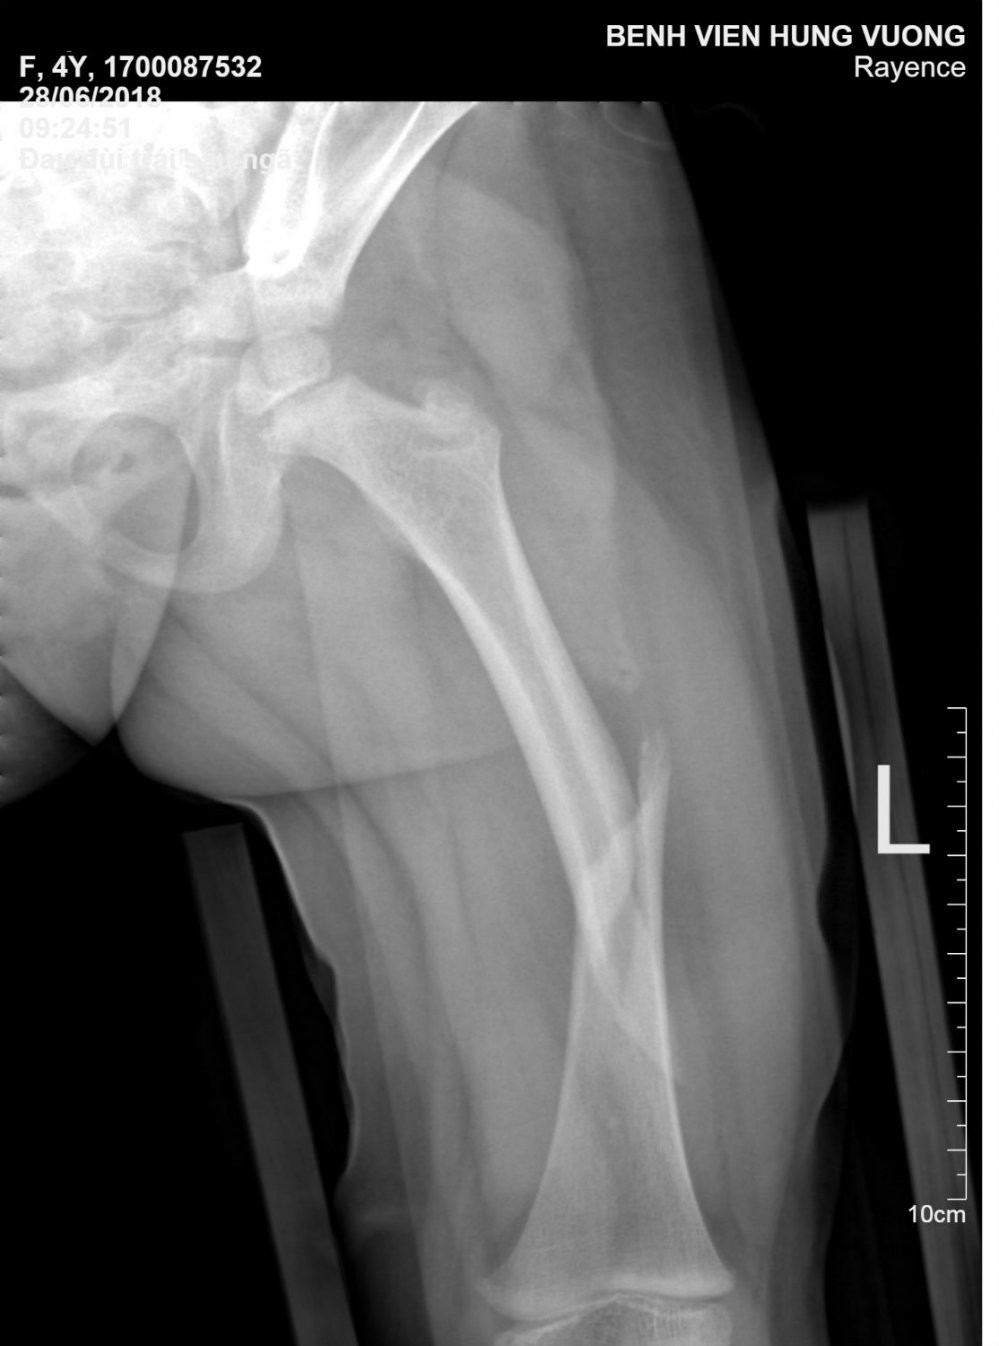

Ngay lập tức các bác sĩ cố định chân trái của bệnh nhi bằng nẹp gỗ và băng gạc vô trùng. Bệnh nhi được chỉ định làm cận lâm sàng cần thiết. Kết quả chụp XQ đùi trái cho thấy hình ảnh gãy di lệch 1/3 xương đùi trái.

Hình ảnh XQ gãy 1/3 xương đùi trái bệnh nhi L.